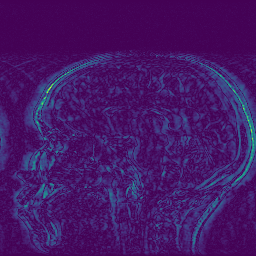

EPN is utilized to provide edge priors for later reconstruction, so the quality of the predicted edges is very important. In Fig. 10, we provide some qualitative results of the predicted edges of EPN on three multi-coil datasets. Among them, the GT edges are extracted using the Sobel operator. As can be seen from the images, our proposed EPN can predict an approximate contour for the overall subject and can reconstruct accurate edges close to the GT edges under two acceleration factors. This fully verifies the effectiveness and excellence of the proposed EPN.

(a)

(b)

(c)

(d)